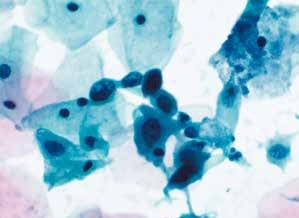

癌细胞成团排列,细胞核异型性明显,染色质粗颗粒状,胞质蓝染,高核质比,肿瘤素质可见。

图4-69 非角化型鳞癌(高倍、液基、巴氏染色)

癌细胞成团排列,圆形、梭形,胞核深染,染色质粗颗粒状,核质比高,肿瘤素质可见。

图4-70 非角化型鳞癌(高倍、液基、巴氏染色)